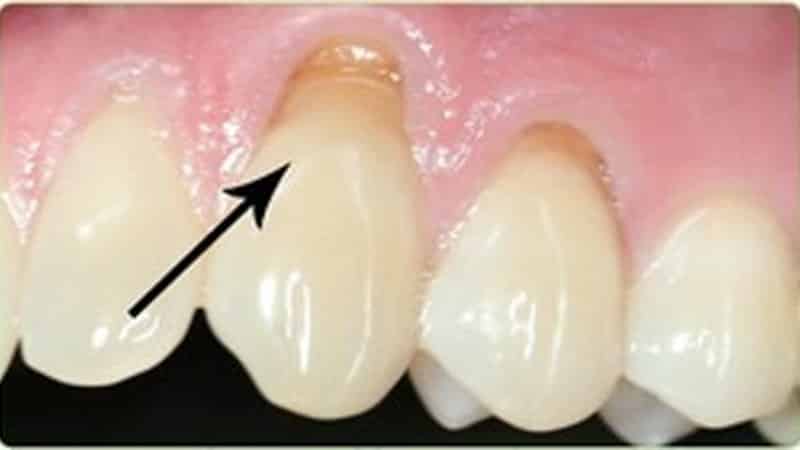

Клиновидный дефект представляет собой некариозное повреждение твердых тканей зуба, при этом такие образования имеют характерную клиновидную форму и располагаются в области шейки зуба.

Чаще всего данный дефект наблюдается на передних зубах, клыках и премолярах. Внешне он напоминает уступы или наросты в виде клина, которые не изменяют своего цвета, за исключением случаев глубокого поражения эмали.

С течением времени в области шейки зуба появляются неглубокие щели, которые постепенно принимают клиновидную форму. Обычно эти щели располагаются симметрично на зубах одной челюсти, в то время как случаи единичных поражений встречаются крайне редко.